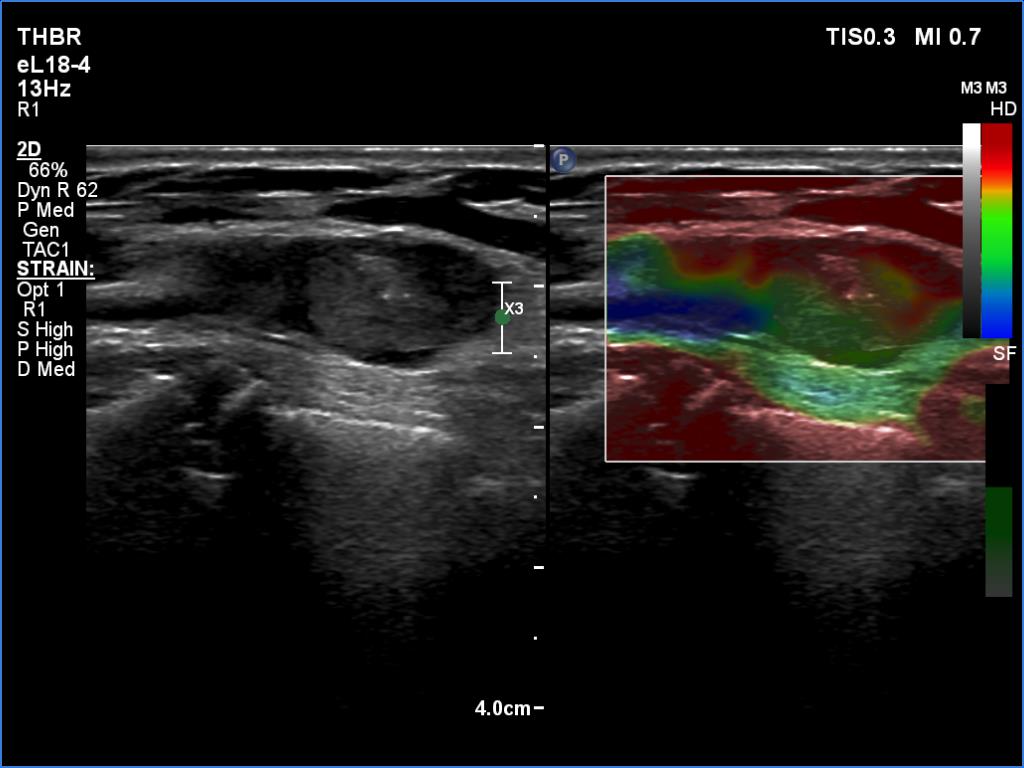

Graves' disease - case 169

Follow-up investigation 6 months after first visit (ultrasonographic picture 9)

Left lobe, longitudinal scan, elastography. Compared with the dorsal extralesional part of the lobe, the lesion is harder.